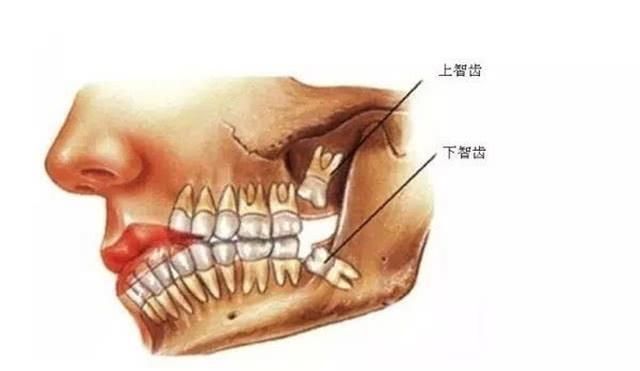

智齿是人成年后才开始进行生长的,是人一生中最后长出的牙齿,并且所生长的地方也是口腔的最深处,这样就会让我们每天的清洗工作变的特别的困难,刷牙的时候往往不能很好地刷到智齿这一块,大家肯定都有过出现紧急情况导致一天或者两天没有刷牙的情况出现的,打个哈欠的时候肯定也感受过味道。这就是为什么拔出来的智齿会这么臭的原因之一!

智齿的发炎也是因为这些引起的,疼到大家可能生活都不能自理的时候就会到口腔医院去进行拔出了,有些没有严重到需要拔牙的也会有很多医生说平时需要多注意清理的问题,让大家刷牙都估计到上下的后槽牙,同时也会让大家多漱口来保持口腔的清洁。智齿如果不好好管理真的会让人痛不欲生的,出现过问题或者还没有出现问题的朋友也需要多按照医生说的口腔清理去做呢!